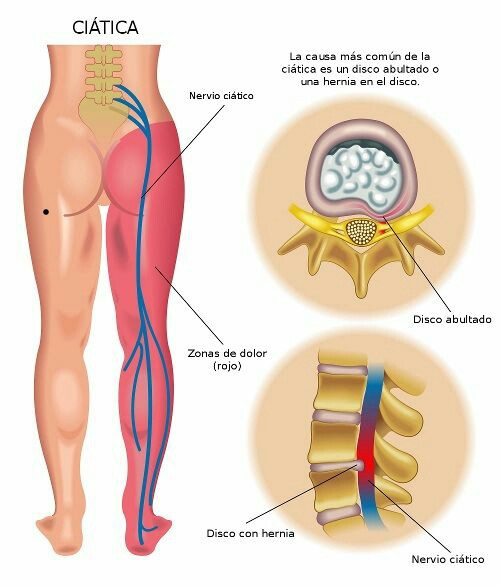

A veces de entrada pero otras en horas o en días, el dolor se irradia a una de las extremidades constituyendo un síndrome ciático y caracterizado por dolor en el trayecto del nervio y / o sensación de hormigueo o acorchamiento. El dolor suele aumentar al toser, estornudar, permanecer quieto de pie o al sentarse.